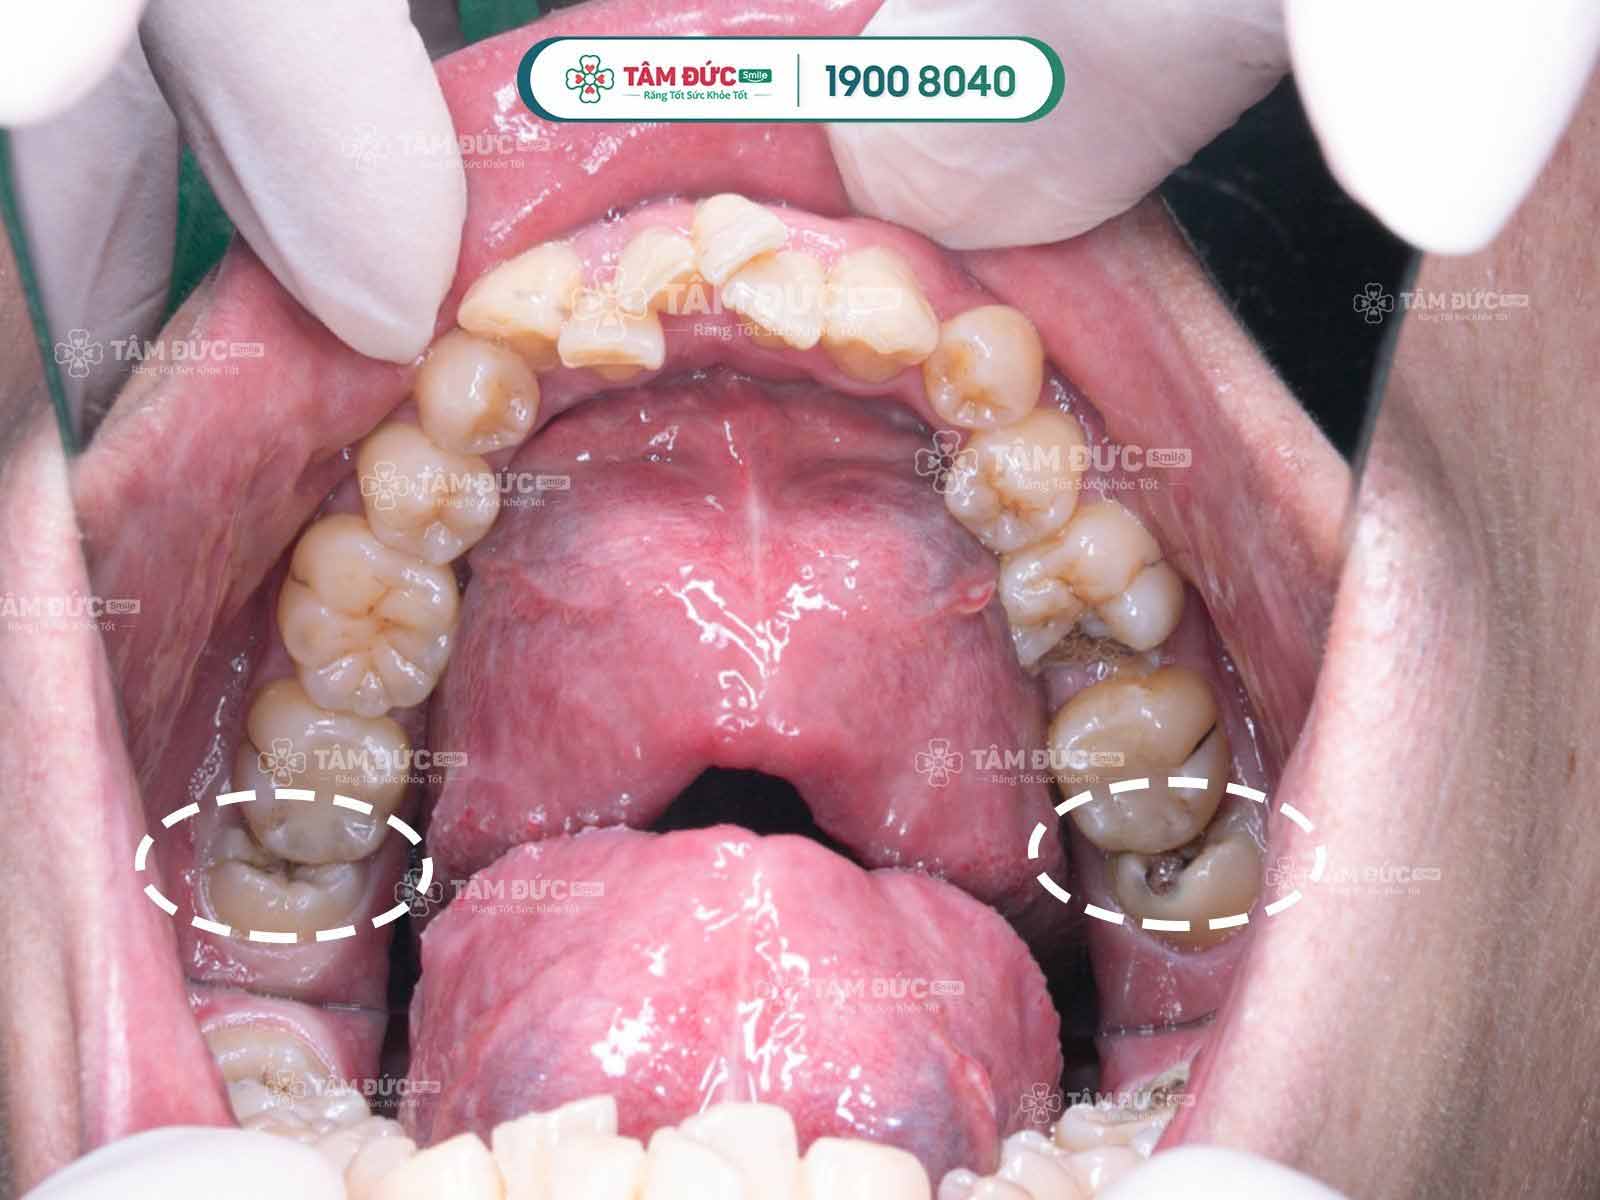

Cần phải nhổ răng khôn mọc lệch càng sớm càng tốt

Tác hại của việc răng khôn mọc lệch:

- Thức ăn sẽ nhồi nhét giữa răng khôn và răng kế bên nếu không vệ sinh được sẽ gây hôi miệng, sâu răng, nghiêm trọng sẽ gây viêm tủy răng số 7 kế bên.

- Răng khôn mọc đâm vào răng kế bên làm cho các răng cửa phía trước dồn lại, chen chúc lệch lạc mất thẩm mỹ và sai khớp cắn.

- Qua kết quả chụp phim thấy răng khôn mọc lệch, đâm vào răng số 7

- Nướu chỗ răng khôn thường bị nhiễm trùng sưng đau lặp đi lặp lại nhiều lần.

- Nhiễm trùng răng khôn kéo dài gây hoại tử xương, viêm mô tế bào, sưng mặt, một số ít trường hợp chuyển sang ung thư phải cắt xương hàm.